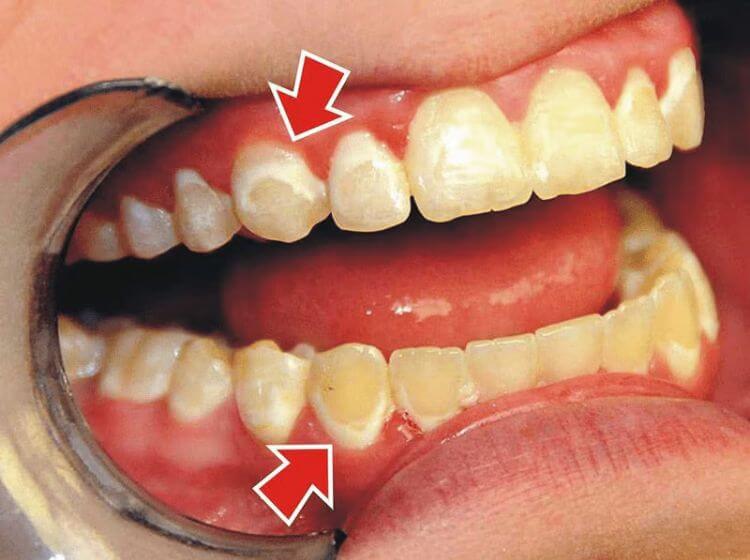

– Xuất hiện mảng bám ở răng: Khi lợi bị viêm, những mảng bám màu vàng hoặc nâu hình thành trên bề mặt răng gần đường viền lợi.

– Sưng tấy lợi: Lợi bị viêm sẽ sưng phồng, nhìn bằng mắt thường sẽ thấy căng bóng và che phủ một phần thân răng.

– Tụt lợi chân răng: Viêm lợi lâu ngày dẫn đến tụt lợi làm lộ phần chân răng, gây ê buốt khi ăn đồ nóng, lạnh.